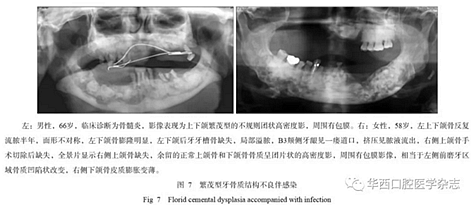

牙骨質(zhì)結(jié)構(gòu)不良具有多樣性的影像學(xué)特征,所以在臨床上也表現(xiàn)為不同的癥狀,由于該疾病生長比較緩慢,患者在未出現(xiàn)癥狀前經(jīng)常不會(huì)來就診。當(dāng)患者出現(xiàn)癥狀時(shí)或者醫(yī)生偶然在拍攝片子后發(fā)現(xiàn)根尖暗影,就會(huì)遇到診斷的問題,最常造成診斷不清的是診斷為慢性根尖周炎,按照慣性思維往往首先思考根尖周炎,就采用傳統(tǒng)的根管治療方式進(jìn)行治療,但治療以后發(fā)現(xiàn)根尖的骨質(zhì)改變更加明顯,極端的甚至出現(xiàn)長時(shí)間的癥狀不消失或者不愈,或者形成骨髓炎改變。多發(fā)性或者泛發(fā)性的牙骨質(zhì)結(jié)構(gòu)不良常常造成牙脫落或者拔牙后出現(xiàn)感染,進(jìn)而出現(xiàn)骨髓炎改變,頜骨骨皮質(zhì)密度增高、增厚,為炎性反應(yīng)性增生所致(圖7)。

發(fā)生于后牙的牙骨質(zhì)結(jié)構(gòu)不良常常表現(xiàn)為頜骨膨脹,臨床容易診斷為腫瘤,牙骨質(zhì)結(jié)構(gòu)不良以往被稱為“假性牙骨質(zhì)瘤”就可以表明這類腫瘤的特性,并且往往造成誤診,而病理由于組織切取和牙、骨等硬組織的原因,常常診斷也比較困難,需要結(jié)合X線檢查來確定[1]。對于泛發(fā)性的牙骨質(zhì)結(jié)構(gòu)不良,X線的診斷應(yīng)該更具有優(yōu)勢,尤其是全景片可以清楚地顯示上下頜骨的病變,對于影像的相似性判斷更加容易,而CBCT的優(yōu)勢在于可以清楚了解病變區(qū)內(nèi)的結(jié)構(gòu)、密度、邊界及相鄰牙等結(jié)構(gòu)受影響的變化情況。